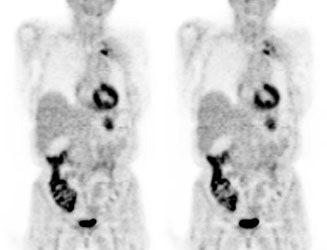

Bladder cancer: Dilute urinary activity in this patient's bladder allowed accurate detection of their bladder cancer (white arrows on CT, black arrows on PET scan). In general, urinary excretion of FDG limits evaluation of urinary tract malignancies, however, hydration and diuresis can improve diagnostic accuracy. |

|

|